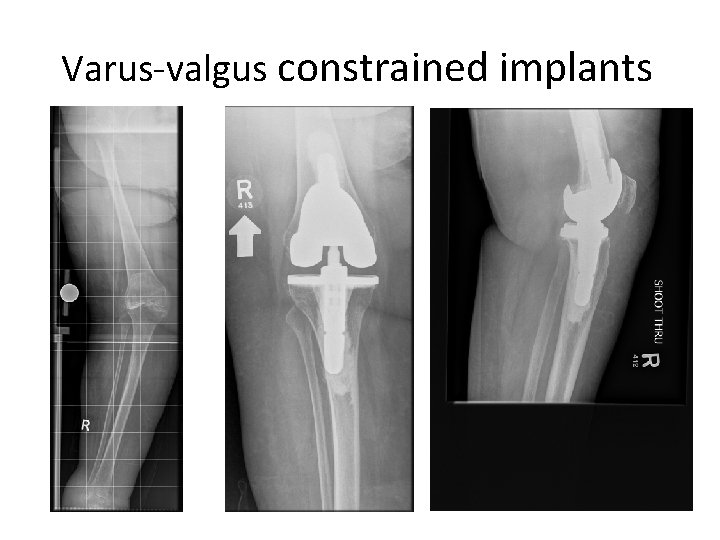

Varus-valgus constrained implants • • Tall tibial post Deep femoral box Stemmed components More inherent coronal plane stability than PS implants

Varus-valgus constrained implants • For primary and revision arthroplasty severe valgus deformities 4 collateral ligament deficiency 4 bone defects 4 flexion-extension imbalances after PS implants 4

Varus-valgus constrained implants Potential disadvantages • need to remove femoral intercondylar bone • higher rates of aseptic loosening • fracture or failure of tibial post

Varus-valgus constrained implants